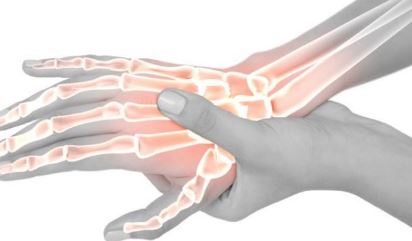

관절은 뼈와 뼈를 연결시켜주며 연골과 활막으로 이루어져 있다. 활막은 관절액을 생성하는 얇은 막으로 류마티스 관절염은 관절 활막의 진속적인 염증반응을 특징으로 하는 만성 염증성 전신 질환이다. 활막의 지속적인 만성 염증반응으로 인하여 관절의 연골 손상, 골 미란이 일어나며 결국은 관절의 파괴가 일어나 기능의 장애를 초래하는 무서운 질병이다.

손가락 류마티스 관절염 증상

1. 손과 발의 관절이 붓고 아프다

2. 아침에 관절이 뻣뻣해져서 펴지지 않고 1시간이상 증상이 지속

3. 피곤함과 열감